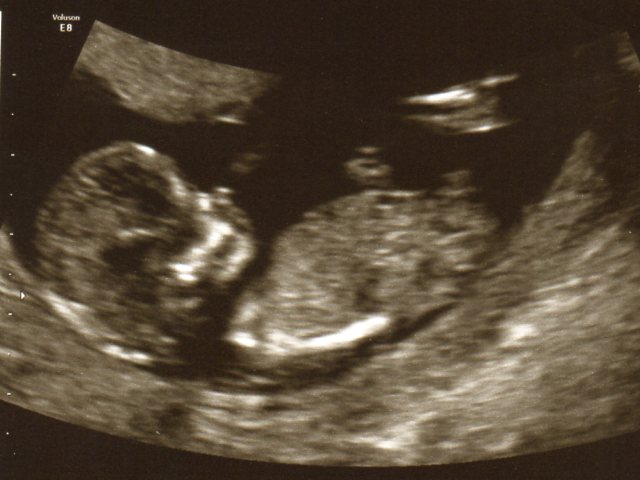

Just for a bit of fun I had a scan at 12 weeks and 21 weeks and was wondering could you tell the sex of a baby by looking at the scan pics? Please see below I have heard of the "nub theory" don't no how accurate it is. First 2 scan pictures are at 12 weeks last one is at 21 weeks.

12 Weeks

Attachment 13125

Attachment 13126

Hi thanks for the reply. Yes in the 3rd picture (21 weeks) can't really tell also was wondering does it matter on the positioning of the baby? I mean if the baby is not horizontal and is at a bit of a vertical angle can it make a flat nub look pointing up?

I agree, looks like a lil boy from the 12 week shots, no gender seen in the 20 weeks!! Baby should be laying as flat as possible for a more accurate guess.

I agree the 12 week scan has a clear shot of a boy nub. I can't see anything on the 20 week scan. Potty shots are better on 20 week scans.